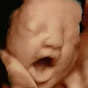

A New Conception 4D Ultrasound Studio logo A New Conception 4D Ultrasound Studio 8,820 4,467,370 172 US View on YouTube